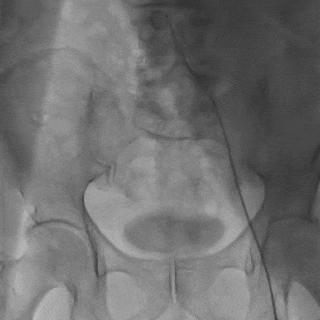

入路选择:22F大鞘置入;右侧股动脉主入路,超硬导丝支撑下植入大鞘。

外周造影检查,血管无损伤